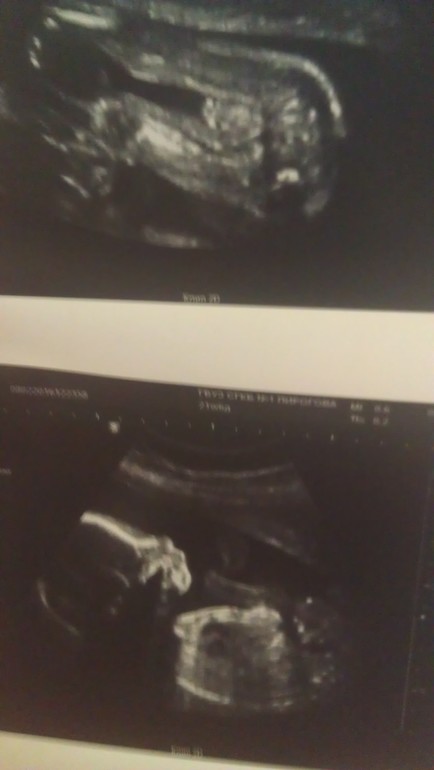

Точно ли мальчик?

Вопросы про УЗИ, обследования и анализы: что, где, как, когда?Как думаете точно ли мальчик? узи в 22 недели

Очень сложно понять... У нас мальчик, но там на всех УЗИ начиная с 14 недель было более чем ясно ((:

Сложно сказать)) бывает что мошонка складывается так что губки напоминает, а бывает что губки торчат как мошонка))) пока "хвостик" не увидите сложно сказать)))